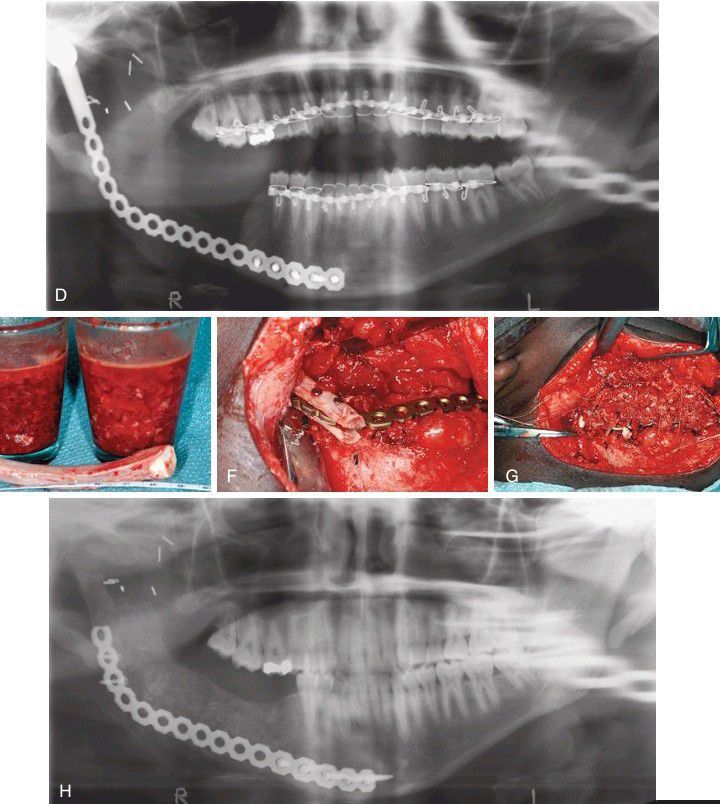

(D) Postoperative panoramic radiograph showing bone plate in place. After allowing 6 to 8 weeks for healing of the oral soft tissues, mandibular reconstruction was undertaken. (E) A rib with some of the costal cartilage attached to one end and particulate bone from the ilium were obtained. (F) The condylar prosthesis was removed from the end of the bone plate, and the body of the rib was grooved and placed into the glenoid fossa, surrounding the bone plate. (G) The mandibular ramus and posterior body were reconstructed by packing particulate bone into the defect. (H) Panoramic radiograph taken 6 months later shows good consolidation of the graft.